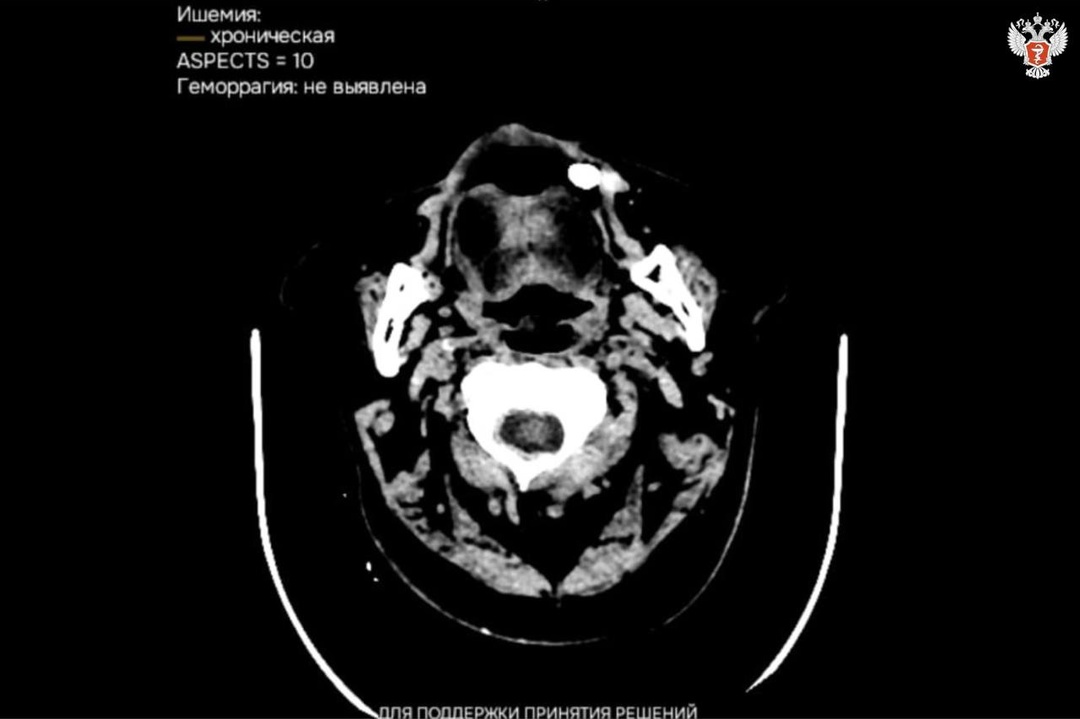

🖥 В медучреждениях Калмыкии внедряются сервисы с ИИ для расшифровки исследований

Искусственный интеллект анализирует любое исследование всего за 15 минут.

🩻 На сегодняшний день с использованием ИИ обработано более 7 тыс. исследований, патологии выявили в более 3 тыс. случаях.

Эти результаты свидетельствуют о высокой эффективности внедрения технологий в медицинскую практику, способствующих своевременному

обнаружению заболеваний и повышению точности диагностики.

🖥 Отметим, что в декабре 2024 года медучреждения Калмыкии подключилась к платформе, объединяющей 17 сервисов для анализа КТ, рентгенографии, маммографии и флюорографии.